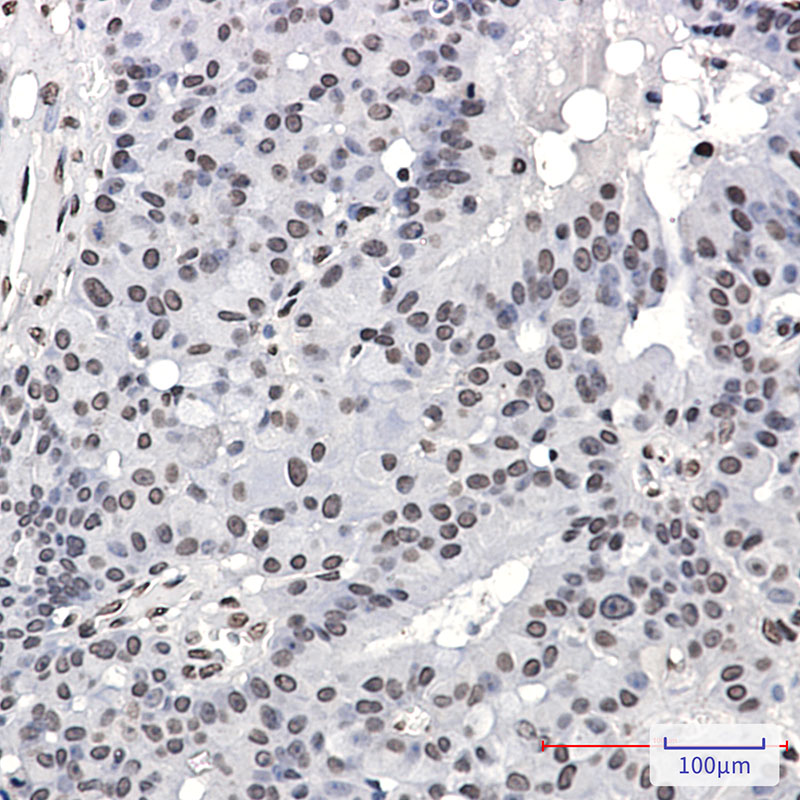

- Immunohistochemistry analysis of paraffin-embedded Human breast cancer using PML Protein (Phospho-Ser518) antibody.High-pressure and temperature Sodium Citrate pH 6.0 was used for antigen retrieval.